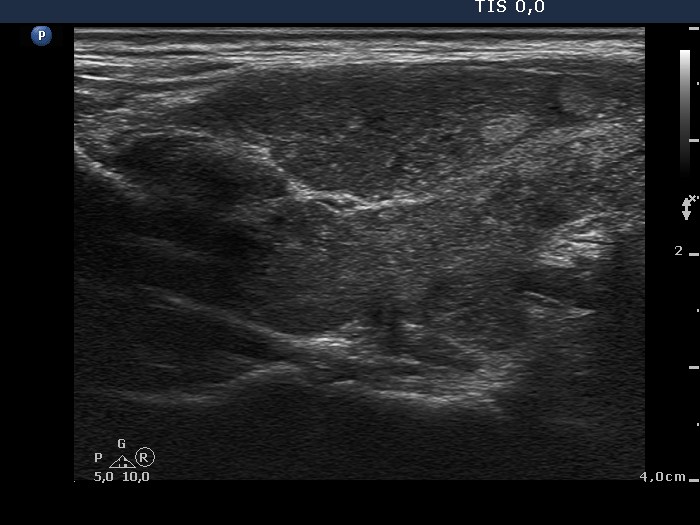

Present examination (ultrasonographic picture 7)

Right lobe, another longitudinal scan.